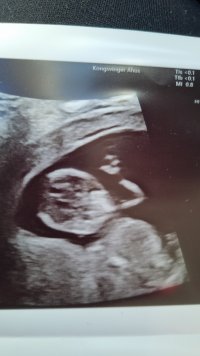

Jeg venter tvillingerIngen som skal få beskjed om at der er to i magen i denne termingruppa da?Noen som har to på følelsen?

Gratulerer så myeJeg venter tvillingerVi har egentlig termin helt i starten av desember, men det er jo ganske uvanlig å gå helt til termin med to, så det blir nok noen novemberkids på oss! Får se om jeg klarer å være aktiv i to termingrupper